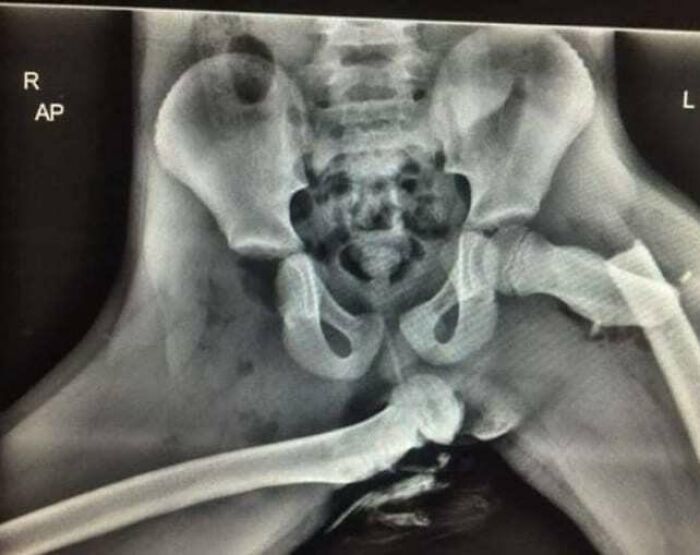

#14 Horrifying X-Ray Shows Why You Should Not Put Your Feet On Car Dashboards

Image credits: medicalpedia